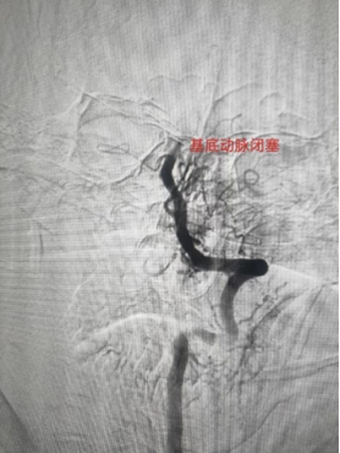

2、基底动脉栓塞,急诊导管抽栓+动脉溶栓1例;